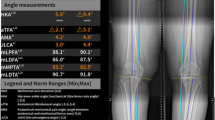

In this Health Insurance Portability and Accountability Act (HIPAA)-compliant retrospective study, radiographs were obtained to develop a deep-learning algorithm. The algorithm developed with two U-Net models measures LLD using the difference between the bilateral iliac crest heights. For performance evaluation of the algorithm, 300 different radiographs were collected and LLD was measured by two radiologists, the algorithm alone and the model-assisting method. Statistical analysis was performed to compare the measurement differences with the measurement results of an experienced radiologist considered as the ground truth. The time spent on each measurement was then compared.

Of the 300 cases, the deep-learning model successfully delineated both iliac crests in 284. All human measurements, the deep-learning model and the model-assisting method, showed a significant correlation with ground truth measurements, while Pearson correlation coefficients and interclass correlations (ICCs) decreased in the order listed. (Pearson correlation coefficients ranged from 0.880 to 0.996 and ICCs ranged from 0.914 to 0.997.) The mean absolute errors of the human measurement, deep-learning-assisting model and deep-learning-alone model were 0.7 ± 0.6 mm, 1.1 ± 1.1 mm and 2.3 ± 5.2 mm, respectively. The reading time was 7 h and 12 min on average for human reading, while the deep-learning measurement took 7 min and 26 s. The radiologist took 74 min to complete measurements in the deep-learning mode.

Supplementary file5 Online Supplementary Material 2 Success and failure in the deep-learning measurement. Teleroentgenograms in (a) a 15-year-old boy and (b) a 13-year-old boy. In a successful case (a), the deep-learning algorithm recognized the bilateral iliac crests and measured leg length discrepancy by calculating height difference (black arrow) between the highest points of the recognized bilateral iliac crests (white dotted line). On the other hand, in (b), the deep-learning algorithm failed to recognize correct iliac crest contour and measured height difference (white arrow) between the highest points of the recognized contour (white dotted line). The correct leg length discrepancy is the height difference between the upper white dotted line and the black dotted line (black arrow) (PNG 943 KB)